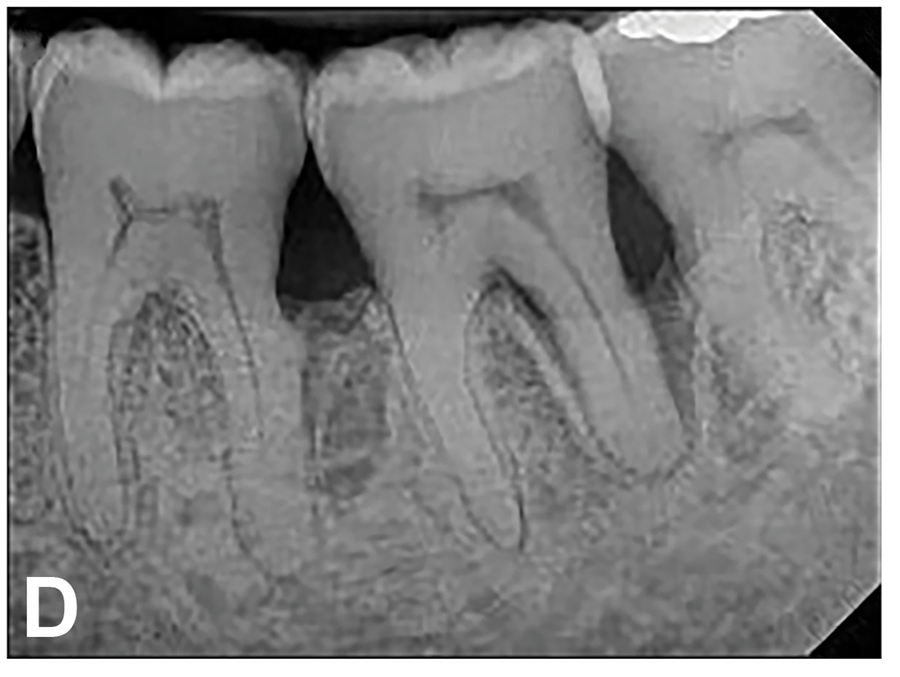

(7.) Progressive improvement in bone quality, quantity, and morphology during each time period, especially in the furcation area of tooth No. 18, which shows a noticeable narrowing of the width of the bony defects, slight apical resorption of the distal root of tooth No. 18, and the encasing of residual cementum on the distal root of No. 19 by new bone formation. Periapical radiographs were taken of teeth Nos. 17, 18, and 19 on June 25, 2016, January 28, 2017, August 23, 2019, and September 4, 2020, respectively, the final of which was taken after almost 5 years post-initial scaling and root planing and alternating supportive periodontal maintenance.

Figure 7

(8.) Progressive improvement in bone quality, quantity, and morphology during each time period, especially in the furcation area of tooth No. 18, which shows a noticeable narrowing of the width of the bony defects, slight apical resorption of the distal root of tooth No. 18, and the encasing of residual cementum on the distal root of No. 19 by new bone formation. Periapical radiographs were taken of teeth Nos. 17, 18, and 19 on June 25, 2016, January 28, 2017, August 23, 2019, and September 4, 2020, respectively, the final of which was taken after almost 5 years post-initial scaling and root planing and alternating supportive periodontal maintenance.

Figure 8

(9.) Progressive improvement in bone quality, quantity, and morphology during each time period, especially in the furcation area of tooth No. 18, which shows a noticeable narrowing of the width of the bony defects, slight apical resorption of the distal root of tooth No. 18, and the encasing of residual cementum on the distal root of No. 19 by new bone formation. Periapical radiographs were taken of teeth Nos. 17, 18, and 19 on June 25, 2016, January 28, 2017, August 23, 2019, and September 4, 2020, respectively, the final of which was taken after almost 5 years post-initial scaling and root planing and alternating supportive periodontal maintenance.

Figure 9

(10.) Progressive improvement in bone quality, quantity, and morphology during each time period, especially in the furcation area of tooth No. 18, which shows a noticeable narrowing of the width of the bony defects, slight apical resorption of the distal root of tooth No. 18, and the encasing of residual cementum on the distal root of No. 19 by new bone formation. Periapical radiographs were taken of teeth Nos. 17, 18, and 19 on June 25, 2016, January 28, 2017, August 23, 2019, and September 4, 2020, respectively, the final of which was taken after almost 5 years post-initial scaling and root planing and alternating supportive periodontal maintenance.

Figure 10

The patient's periodontal disease improved with initial nonsurgical periodontal therapy that involved scaling and root planing. This initial treatment was followed by only SPT every 3 months. Despite treatment, residual deep periodontal probing depths remained, so a decision was made to maximize improvements with nonsurgical therapy and to reassess as needed to determine whether surgical intervention was appropriate. After almost 5 years of SPT and good patient compliance with plaque control and supportive care, the periodontium was stable. Because of the resulting bone formation and improvements in clinical attachment levels (Figure 7 through Figure 13), it was determined that periodontal surgical intervention was not necessary.

In the case report presented, treatment with nonsurgical therapy for 5 years effectively halted destruction and led to bone regeneration and improved clinical attachment levels. Although the primary etiology of periodontal disease is well documented, secondary etiologic and contributing factors are numerous.16 After initial therapy in the current case, there was radiographic evidence of a hypercementosis-like lesion on the distal root of tooth No. 19 (Figure 7 through Figure 10). Hypercementosis is a nidus for plaque accumulation leading to disease progression; however, the presence of this lesion did not explain the disease severity observed for tooth No. 18. Chronic periodontitis is the most widespread form of periodontal disease, and nonsurgical periodontal therapy is the most common type of therapy.17 Scaling and root planning is the gold standard for periodontal treatment. When performed meticulously, they result in improvement of clinical parameters through changes related to tissue shrinkage, long junctional epithelium, new attachment, and in rare circumstances, regeneration.18 The use of nonsurgical periodontal therapy for treatment of periodontal disease requires that the timing for re-evaluation is customized for each patient. Because individuals heal at different rates, the overall medical condition, nutritional intake, environmental and social risks factors, local factors, and colonization of pathogenic bacteria of patients should be considered.7,8 Some patients cannot afford, or choose not to pursue, surgical periodontal therapy. For these patients, clinicians should delay surgical decisions until periodontal risk factors are addressed and nonsurgical efforts are exhausted.

Although rare, the radiographic evidence in the current case indicated that nonsurgical therapy effectively halted the destructive effects of severe chronic periodontitis and led to bone regeneration, thereby eliminating the need for surgery. The current case also showed that nonsurgical periodontal therapy may lead to desirable outcomes for patients with severe chronic periodontal disease if the patient is compliant with plaque control, supportive periodontal therapy is provided, etiological and risk factors are eliminated, and the body is given adequate time to heal.11 An additional factor that may have influenced the positive outcome of the current case was the patient's favorable health status.